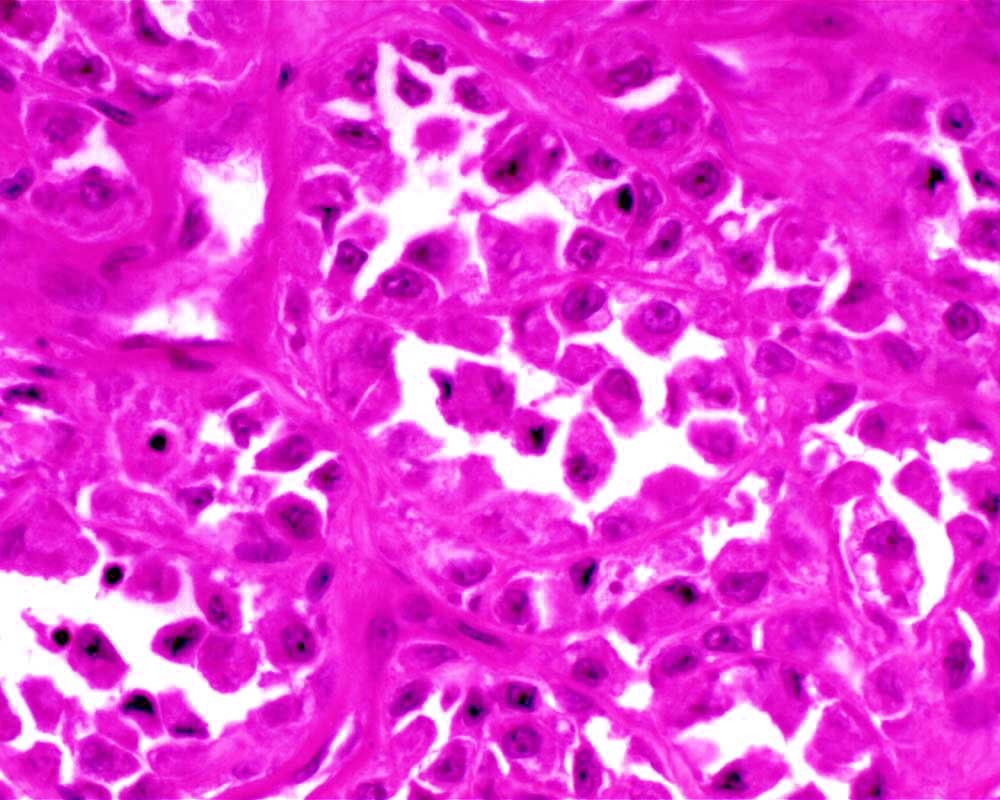

Case: ThighMass

Final Diagnosis: